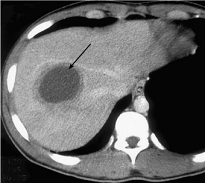

Первичные и метастатические опухоли печени имеют

вид округло-овальных узлов пониженной плотности, хорошо накапливают контрастное

вещество. Определенные трудности вызывают случаи дифференциальной диагностики с

гемангиомами печени, внутривенное контрастирование при этом является

обязательным техническим приемом. Липомы имеют отрицательные значения плотности

и не пересекаются с другими предположениями.

КТ печени КТ киста селезенки

КТ почек